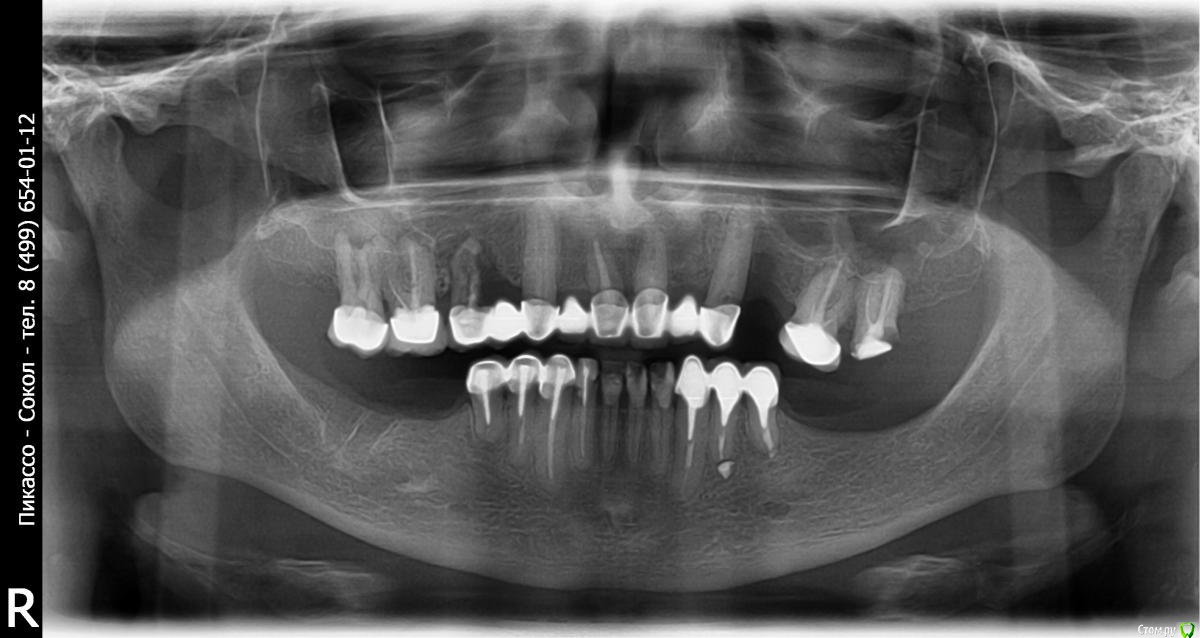

У меня в данный момент проблема с зубами и мне необходима помощь в выборе тактики протезирования. В данный момент в связи с воспалением корня зуба, у меня отпилили часть (один зуб с края) верхнего моста и удалили больной зуб. Из-за этого произошла разгерметизация соседнего зуба и мне предлагают теперь снять весь мост, хотя он у меня отлично стоит. Дырка вместо зуба удручающе выглядит...

В нижнем ряду ситуация также грустная...необходимо снять мост и перепротезировать. Во вложении мой панорамный снимок.

а если подробно:

анализ кт

все снимать

что то удалить с заменой имплантами сразу

установить импланты внизу с двух сторон

то что можно сохранить - перелечить

восстановить то что перелечили и временно запротезировать

открыть импланты с пластикой десны, временно нагрузить временными коронками

спротезировать весь рот одним махом